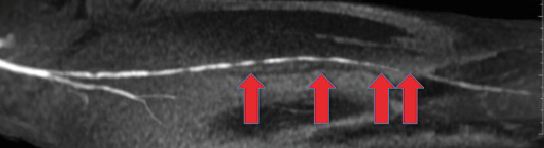

Magnetic resonance angiography is another less invasive alternative to traditional angiography (see right photo). This modality has become more prevalent as the technology and relevant gadolinium contrast protocols have improved.

The reported sensitivity of 94 percent and specificity of 90 percent of MRA in detecting hemodynamically significant lesions in peripheral vasculature is similar to the CTA imaging technique.10 Baum and colleagues performed a blinded, prospective multicenter study of 155 consecutive patients with either rest pain or tissue loss, comparing MRA versus traditional contrast angiography.22 They found that MRA and contrast angiography are approximately equivalent in diagnostic accuracy. Sensitivity in distinguishing patent segments from completely occluded segments was 83 percent for CTA and 85 percent for MRA, and both had 81 percent specificity. For distinguishing near normal segments (suitable as bypass graft termini), CTA was less sensitive than MRA (77 percent versus 82 percent), but more specific (92 percent versus 84 percent). Meissner and coworkers found similar efficacy comparing MRA versus digital subtraction angiography when evaluating the lower leg and foot.23

In comparison to CTA, vessel wall calcification will not cause an artifact on MRA as it shows the natural contrast between blood and the vessel wall. Other advantages are the absence of ionizing radiation and the diminished nephrotoxicity of gadolinium in comparison to iodinate contrast.22 There are many restrictions (such as implanted pacemakers, metallic prosthesis, cardiac life support systems or history of claustrophobia) that would make patients unsuitable candidates for MRA. Magnetic resonance angiography suffers from increased costs and time to perform the study in comparison to CTA. Magnetic resonance angiography imaging also has difficulty when there is a previous metallic stent in the vessel that could falsely appear stenotic or occluded. Researchers have recently associated magnetic resonance angiography with renal failure and systemic nephrogenic sclerosis.23 The modality is also very expensive and not widely available.23